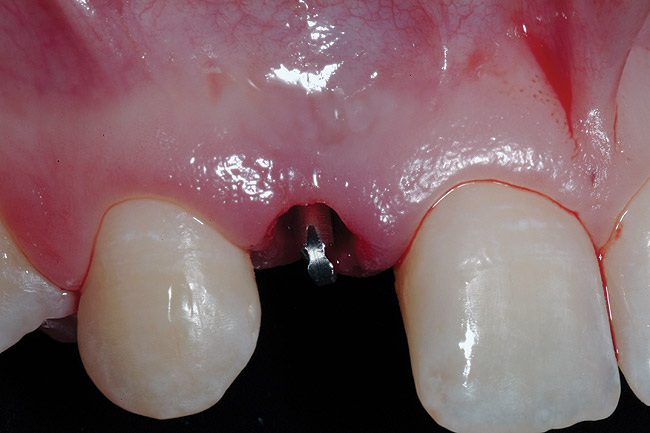

After atraumatic site preparation, two 3-mm diameter by 10-mm in length one-piece implants were seated at the No. 7 and No. 10 sites (Zimmer Dental, Carlsbad, CA) (Figure 9). Note the emergence profile formed by the esthetic recontouring of the crest of the ridge prior to implant site preparation. Confirmation of implant positioning was then verified by placing the TempStent II guide over the surgical sites (Figure 10). Ideally, because the heads of these implants are not wide and they do not lend themselves to gross preparation to reduce the facial aspect, the implants may not be suited for maxilla that has a steep angle. Minor preparation of the head can be performed facially but should be kept to a minimum.

Figure 9  Minimally invasive small-diameter implant placement.

Figure 9